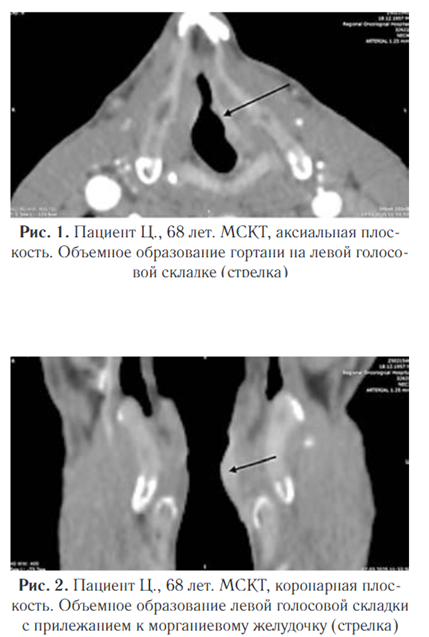

Согласно инструкции, расчет дозы в миллилитрах на килограмм массы тела не предусмотрен. Для взрослого пациента рекомендуется вводить 100–150 мл препарата. В связи с этим мы применяли Ниоскан 350 в дозировке 100 мл для данного пациента. По данным мультиспиральной компьютерной томографии шеи: на левой голосовой складке определяется объемное образование смешанного типа роста, занимающее всю длину голосовой складки, прилежит к морганиевому желудочку (закрыт), вестибулярная складка без признаков роста (рис. 1, 2)

Плотность новообразования в нативную фазу исследования составила 47 HU, в артериальную фазу отмечено равномерное накопление контрастного вещества до 111 HU, в венозную фазу вымывание контрастного вещества — 102 HU. Особое внимание уделялось визуализации степени инфильтрации опухоли в морганиев желудочек и вестибулярную складку, что позволяло объективно оценить степень вовлеченности окружающих тканей и прогнозировать дальнейшее течение патологического процесса. Размеры образования: в аксиальной плоскости 18,5 мм (длина), 4,1 мм (ширина), в коронарной плоскости 17,8 мм (вертикаль) (рис. 3, 4).